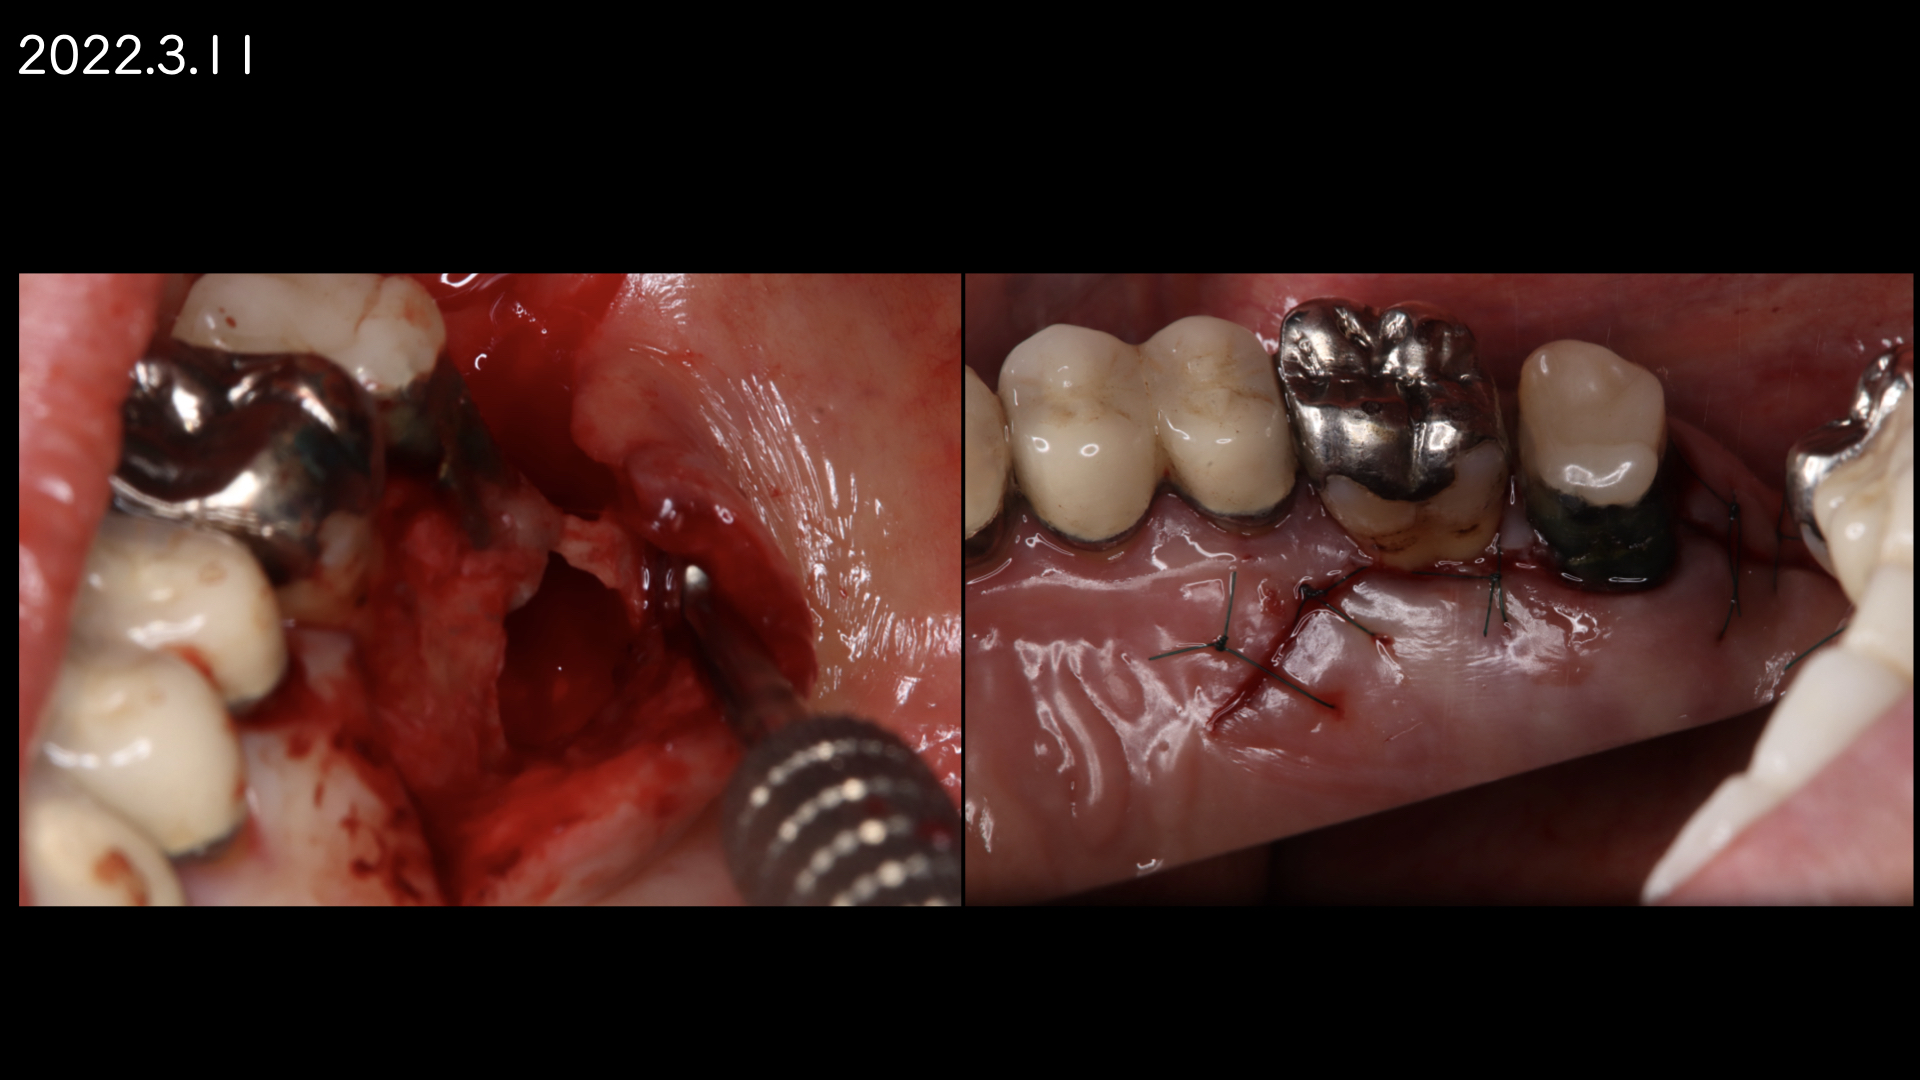

患者さんの都合もあり1年後に歯根端切除(外科的歯内療法)をおこなうことになりました。

論文より今回のケースは安全であると判断し、歯根端切除で対応しました。

切断した歯根です。表面が粗造になっており、感染が根尖孔外にあったことを認めます。

注意しておこないました。